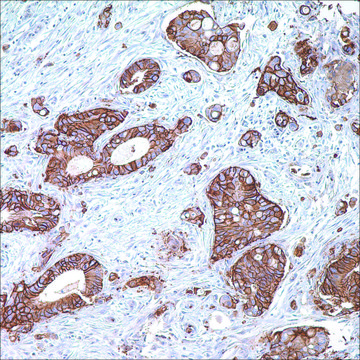

immunohistochemistry (formalin-fixed, paraffin-embedded sections): 1:50-1:200

colorectal carcinoma, mesothelioma

membranous

Glucose transporter type I (GLUT1), a prototype member of GLUT superfamily, is a membrane-associated erythrocyte glucose transport protein. It is a major glucose transporter in the mammalian blood-brain barrier, and also mediates glucose transport in endothelial cells of the vasculature, adipose tissue, and cardiac muscle. GLUT1 is detectable in many human tissues including those of colon, lung, stomach, esophagus, and breast. GLUT1 is overexpressed in malignant cells and in a variety of tumors that include the breast, pancreas, cervix, endometrium, lung, mesothelium, colon, bladder, thyroid, bone, soft tissues, and oral cavity. Immunohistochemical detection of GLUT1 has been shown to discriminate between reactive mesothelium and malignant mesothelioma in more than one study.Anti-GLUT1 is also useful in distinguishing benign endometrial hyperplasia from atypical endometrial hyperplasia and adenocarcinoma.